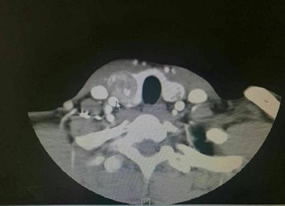

患者CT检查情况 患者CT检查情况 颈部手术切口设计

小庄是在1个月前无意中发现颈部肿大的,在外地某市级医院做了彩超检查,诊断为“双侧甲状腺结节”。随后在当地另一家部队医院做了细针穿刺,病理考虑为良性病变,为 进一步确诊,他慕名来到“医联体”找到综合外科一病区主任兼普外科主任张惠灏为其进行了详细的检查。经查,初步诊断其为右侧甲状腺癌并右侧颈部淋巴结转移,需马上安排 住院检查。随后,经颈部CT增强检查证实了专家的判断,而且还发现了原发灶侵及部分气管,颈部淋巴结转移也比较厉害。鉴于患者年轻,为保证手术的彻底性,专家决定采用改 良术式为患者行全甲状腺切除和右侧功能性颈部淋巴结清扫术。